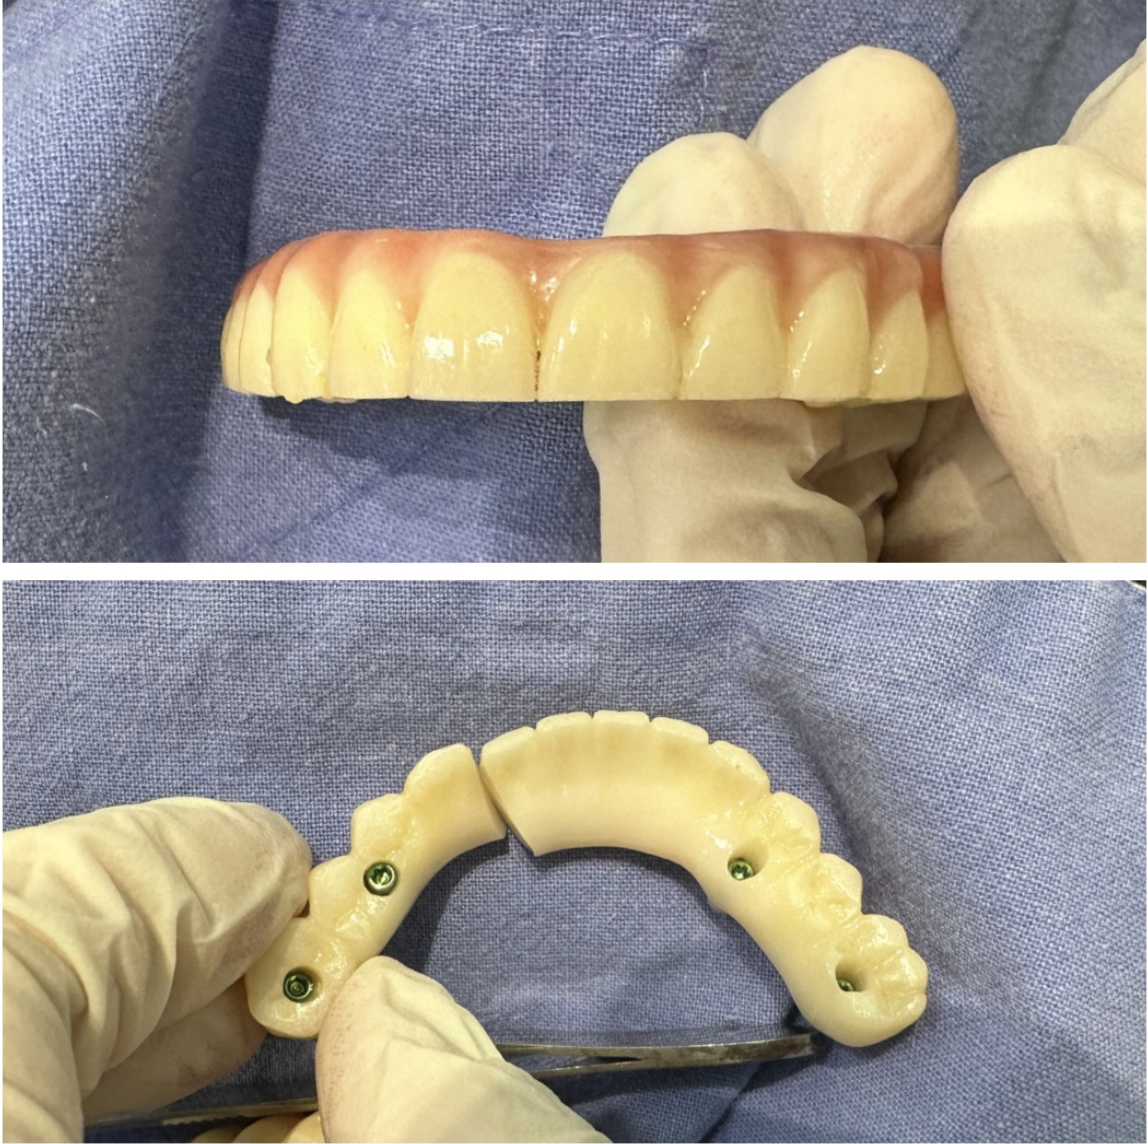

고정식 풀아치

나사로 고정 식이라 넣었다 뺐다 하지 않아요.

Q. 당일날 임시치아 낄수 있나요?

A.

골질이 좋은 경우 고정이 30이상 나온경우엔 가능해요.

하지만 사진처럼 사람마다 골질이 다양해서 무리하면 탈이 날수 있습니다. 개인에 따라 달라요.